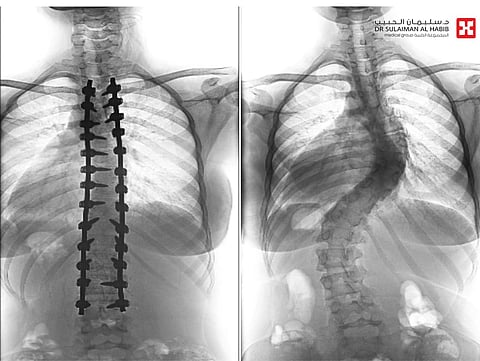

أجرى مستشفى الدكتور سليمان الحبيب بالفيحاء في جدة، بنجاح عملية جراحية معقدة، لتقويم انحراف مزدوج ومتزايد بالعمود الفقري "جنف"، بدرجة "63" و"45"، وتثبيت ودمج الفقرات، لفتاة عمرها "17" عاماً، وأنهت العملية التي استمرت "6" ساعات، معاناة المراجعة مع عدة أعراض حادة استمرت معها لفترة طويلة، ذكر ذلك د. صلاح الدين خليفة استشاري جراحة العظام والعمود الفقري.

وجاءت المراجعة إلى المستشفى وهي تشتكي من تحدب وإنحاء جانبي، قيد حركتها وغير نمط حياتها، وعقب وصولها تم إخضاعها للفحوصات المخبرية وأشعة الرنين المغناطيسي Mri والأشعة السينية X- ray لكامل منطقة الظهر، حيث أكدت النتائج وجود انحراف مزدوج بزاوية "63"، و"45" درجة، وأخضعها الفريق الطبي لعملية جراحية، تم فيها تقويم العمود الفقري باستخدام البراغي والقضبان المعدنية، وتثبيت ودمج الفقرات، واستخدمت في العملية، مجموعة من أحدث الأجهزة الطبية منها الجراحة الملاحية Spinal NavigationSurgery، الميكروسكوب Pantero ومراقبة الأعصاب electrophysiology وساهمت هذه الأجهزة في نجاح التدخل الطبي.

وحولت المراجعة بمؤشرات حيوية مستقرة إلى العناية المركزة ووضعت تحت المراقبة لليلة واحدة، ومن ثم نقلت إلى غرفة التنويم وتحسنت حالتها، حيث تمكنت من المشي بعد "24" ساعة من العملية تحت إشراف اختصاصي العلاج الطبيعي، ومن ثم غادرت إلى منزلها بحالة صحية ونفسية ممتازة بعد "7" أيام، وأكدت فحوصات ما بعد العملية تعديل الميلان مع الحفاظ على سلامة الأعصاب، إضافة إلى أن المراجعة استعادت القدرة على الحركة والمشي بتوازن، والاستلقاء والنوم على ظهرها، فضلاً عن القوام والمظهر الطبيعي، بعد تعديل وضعية الحوض والكتف، كما أن طولها مع النجاح الكبير للتعديل زاد "5" سم. يذكر أن قسم جراحة العمود الفقري بالمستشفى تتوفر فيه أحدث التجهيزات ويقدم رعاية عالية الجودة على يد كفاءات طبية متمرسة، وتمكن خلال فترة الماضية من إنهاء معاناة عدد كبير من حالات انحراف العمود الفقري المعقدة بنجاح.